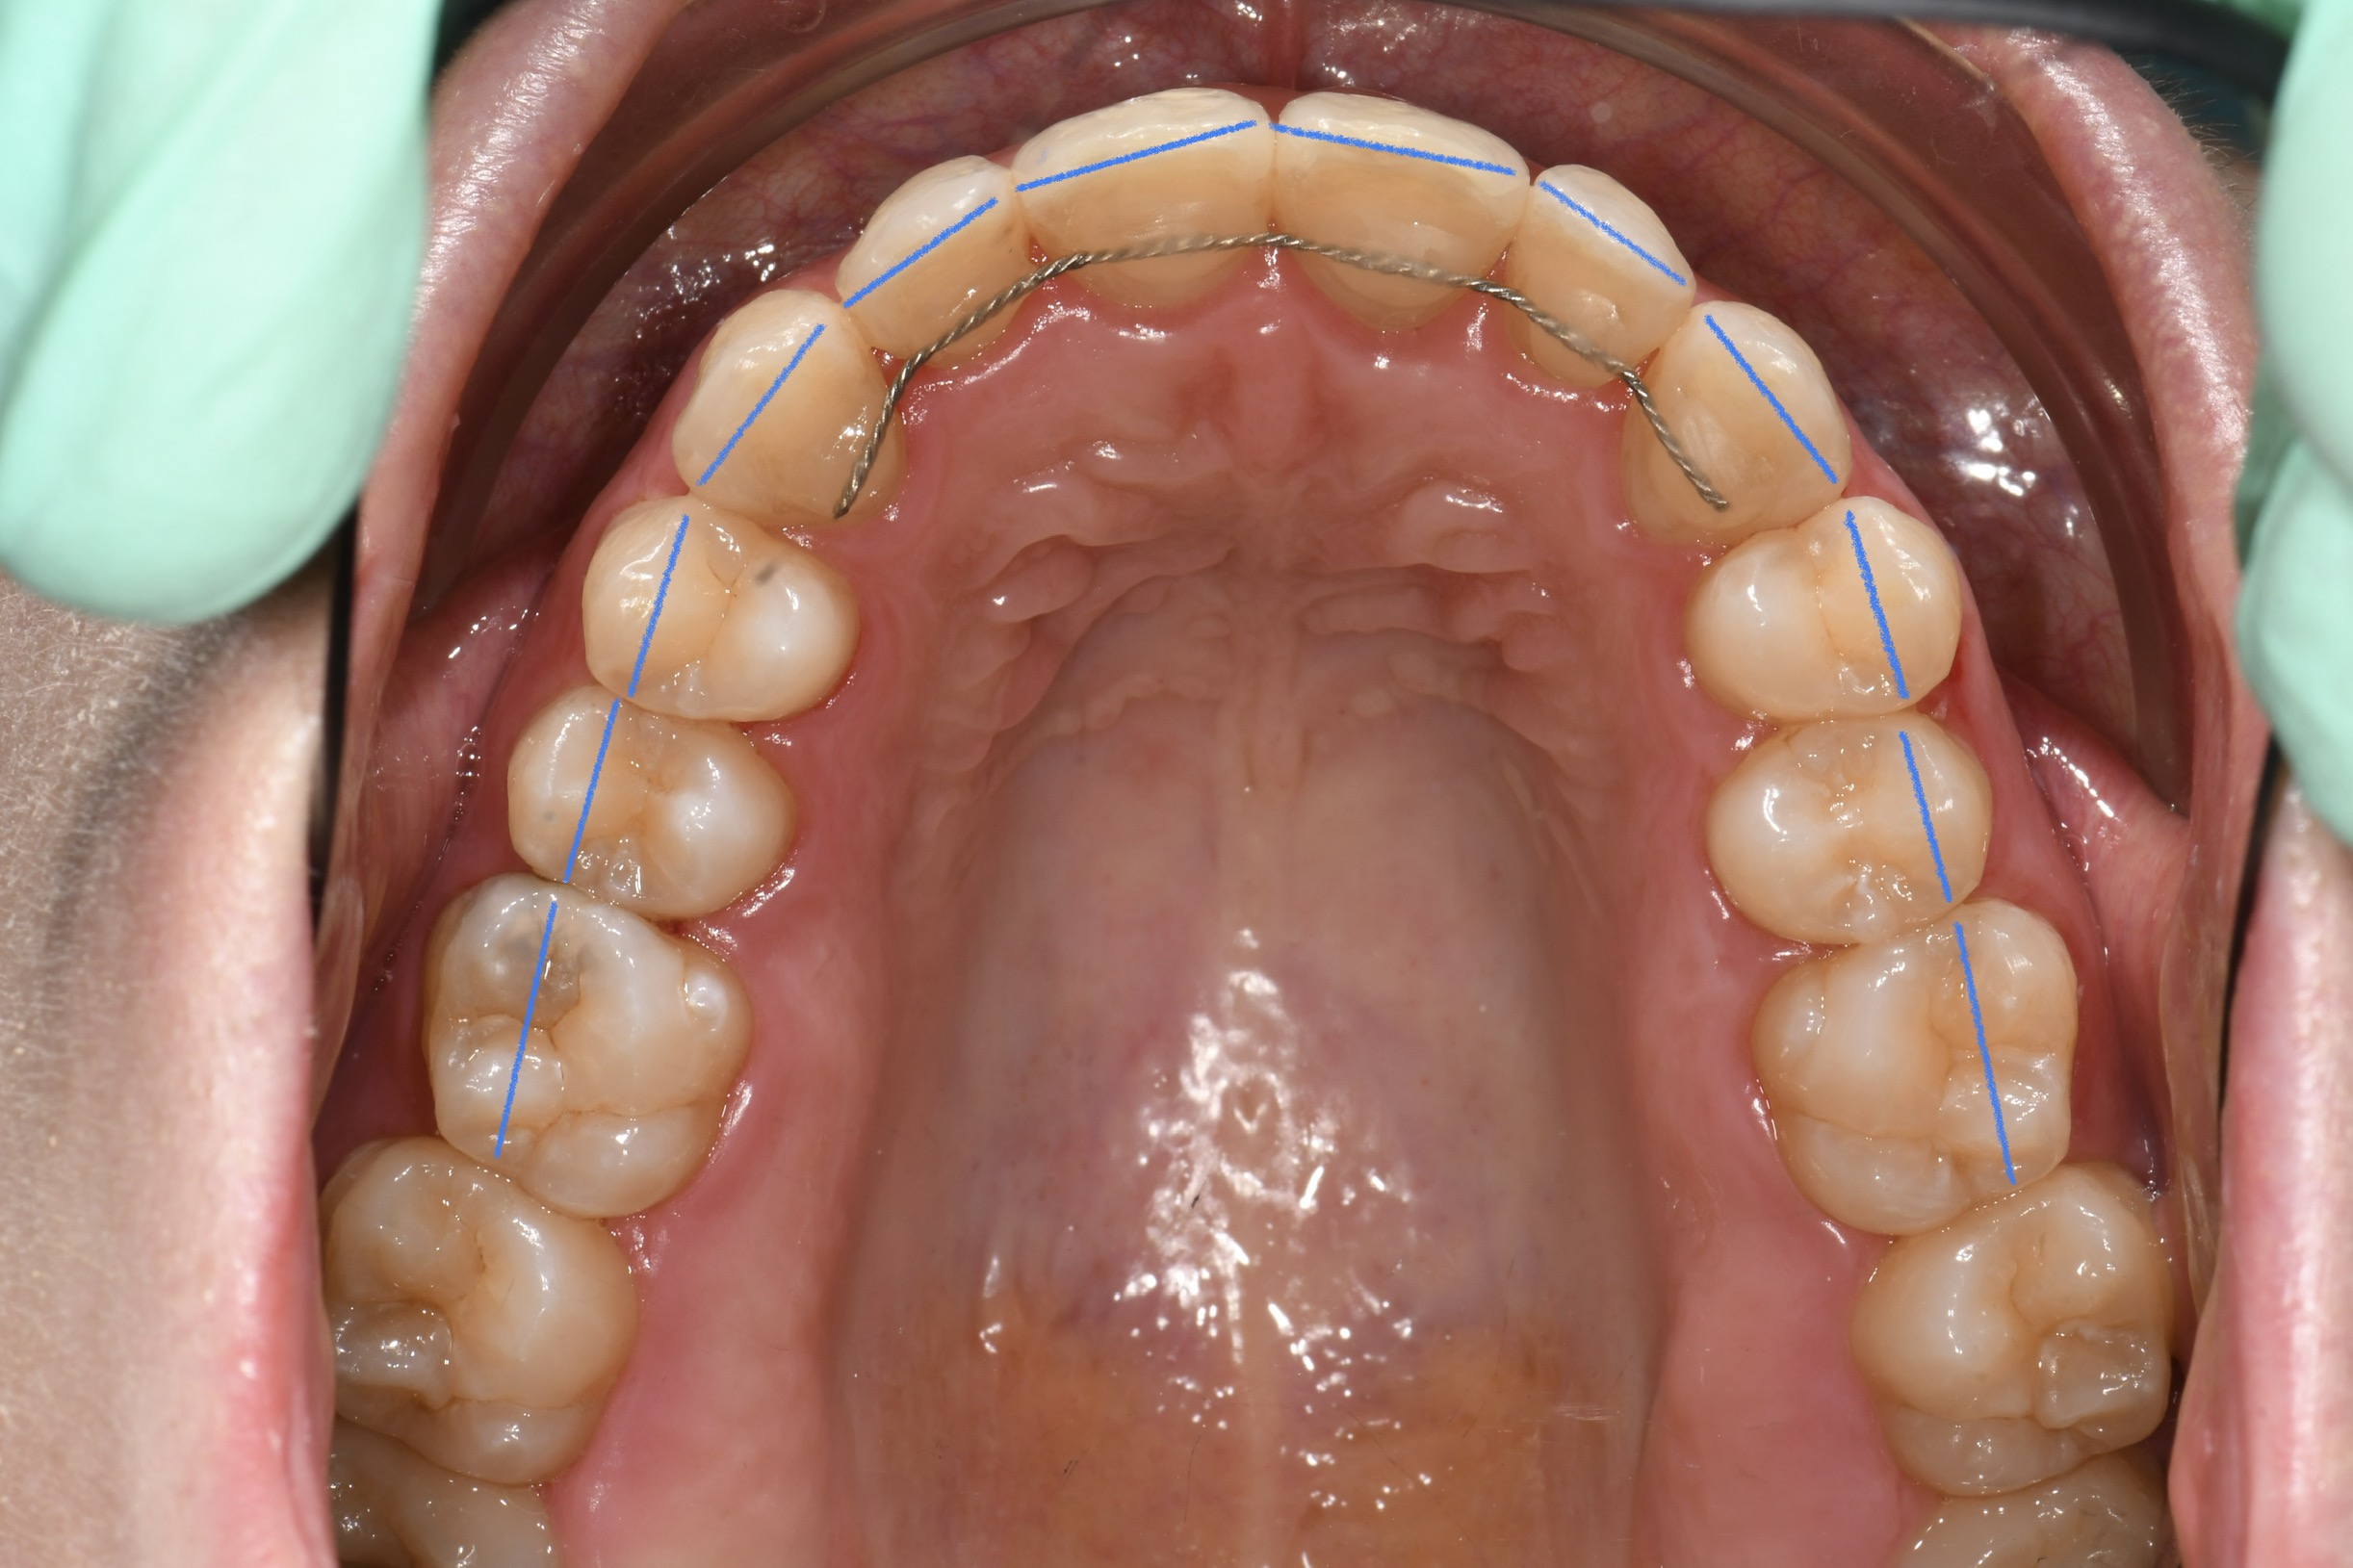

Az elmúlt évekből rengeteg szakmai referenciát tudnánk bemutatni, amelyek különböző fogszabályozási problémákat oldottak meg. Válogatva a több száz esetből, ezen az oldalon olyan képeket, információkat igyekeztünk bemutatni, amelyeknek a segítségével a jövőbeni pácienseinknek azt tudjuk üzenni: A Te fogsorod is lehet gyönyörű!